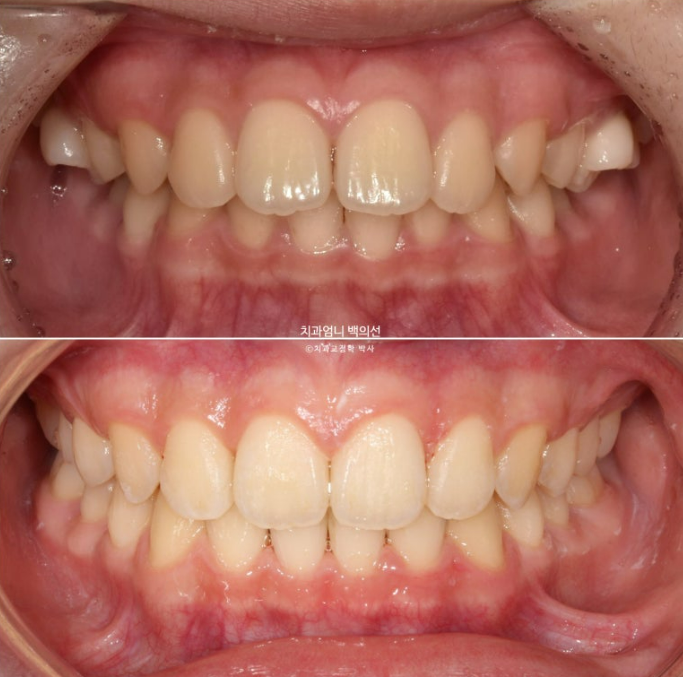

이제 전 후 비교해보겠습니다.

총 치료기간은 1년 2개월 입니다.

24.03~25.05

앞니 돌출의 개선

치근평행도는 좋고 치근흡수는 없습니다.

치아 이동속도는 빠르고 교정 부작용이 적은 것은 어린이교정의 큰 장점입니다.